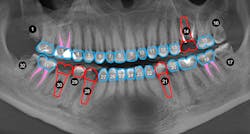

Case review: This 35-year-old female was diagnosed with Sjögren’s syndrome four years ago. She is a cigarette smoker and drinks multiple sodas per day. Her daily oral hygiene is marginal (figures 3–5).

Treatment objectives: Restore or replace all teeth to achieve full function and a natural, healthy-looking smile with a solution that is fixed and will last over the long term (20-plus years).

Today, more than ever, patients expect and hope their dental restoration will solve what has historically been a lifetime cycle of dental problems and expense. In this case, a straightforward, conventional restorative treatment plan that focuses on restoring the patient’s natural teeth may not make the most sense long term. After comparing both restorative paths, the full-arch implant option would likely prove to have a better prognosis, lower cost, and require much less time and fewer appointments.